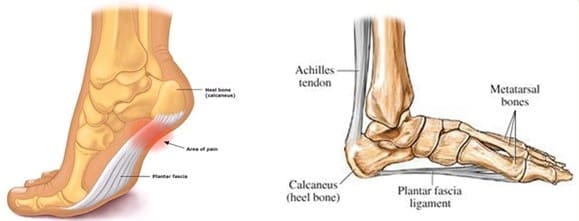

Chronic Plantar Fasciitis

What is it?

Plantar fasciitis is a pain that occurs under the heel or arch. It is a very common condition and can be very painful. It most often occurs in people aged between 40-70 years of age. It affects women and men equally. It is a chronic straining of the plantar fascia ligament. It is not a ‘spur’ or’ tear’.

What is the injury process?

It is thought that the plantar fascia becomes damaged by being stretched too much and being under too much pressure.

The plantar fascia’s function is to hold up the arch of the foot and is therefore under tension when we are standing/walking. Often the tension can increase to a level that damages the fascia – e.g. from increased body weight, or your arch has flattened over time. Sometimes the pressure on the heel can also increase because of these unhelpful loads.